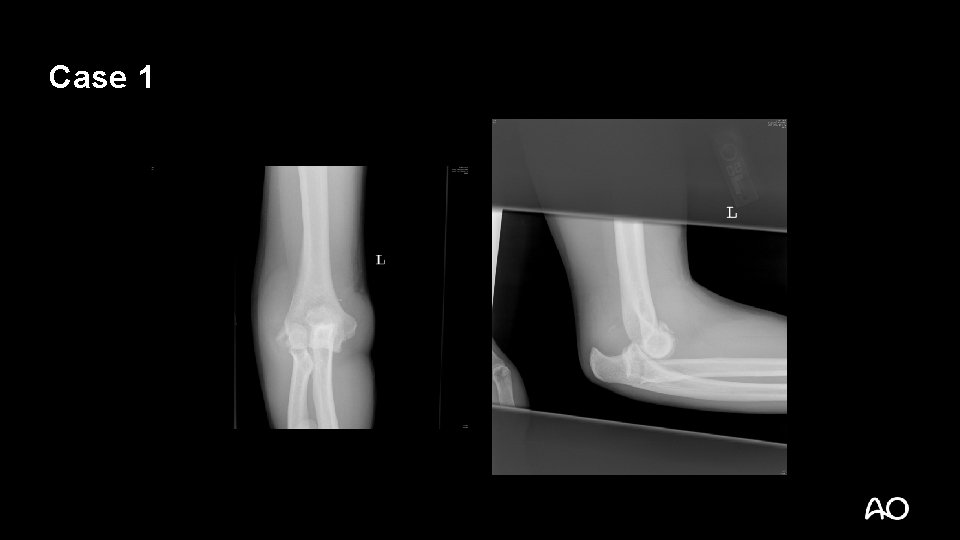

Case 2

Transolecranon fracture dislocation • Not a simple olecranon fracture • Do not treat with tension band wiring • Olecranon fracture with ANTERIOR dislocation but intact proximal radioulnar joint • Ligaments may be intact

Transolecranon—tactic • Extensile posterior exposure • Full-thickness cutaneous flaps: • Can access Kocher (ECUanconeus) interval for radial head repair/replacement if necessary

Transolecranon—tactic • Address coronoid fractures through olecranon fracture line • Anatomically reduce olecranon • Plate-and-screw constructs are often necessary (no tension band) • Normally, ligaments are relatively spared